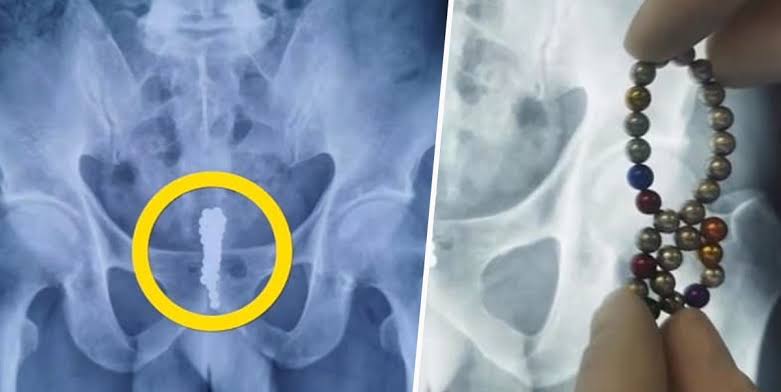

Doktorlar Jiang Hua’yu muayane etti ve röntgen çekti. Manyetik topların iki sütuna hizalanan posterior üretra bölgesinde sıkışıp kaldığını belirlediler

Ardından genç çocuk ameliyata alındı ve yapılan ameliyatla çocuğun penisindeki 53 mıknatıs top çıkarıldı